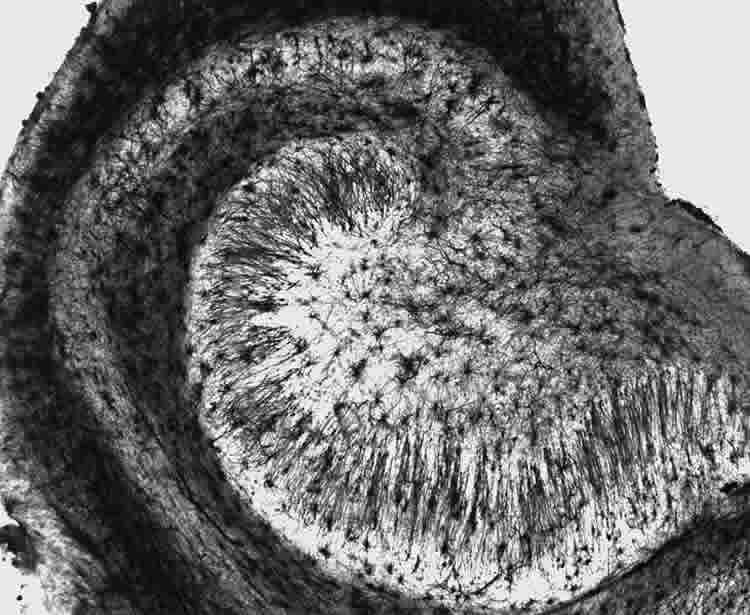

Third, the team discovered that when curiosity motivated learning, there was increased activity in the hippocampus, a brain region that is important for forming new memories, as well as increased interactions between the hippocampus and the reward circuit. “So curiosity recruits the reward system, and interactions between the reward system and the hippocampus seem to put the brain in a state in which you are more likely to learn and retain information, even if that information is not of particular interest or importance,” explains principal investigator Dr. Charan Ranganath, also of UC Davis.

Image Source: The image is credited to MethoxyRoxy and is licensed Creative Commons Attribution-Share Alike 2.5 Generic